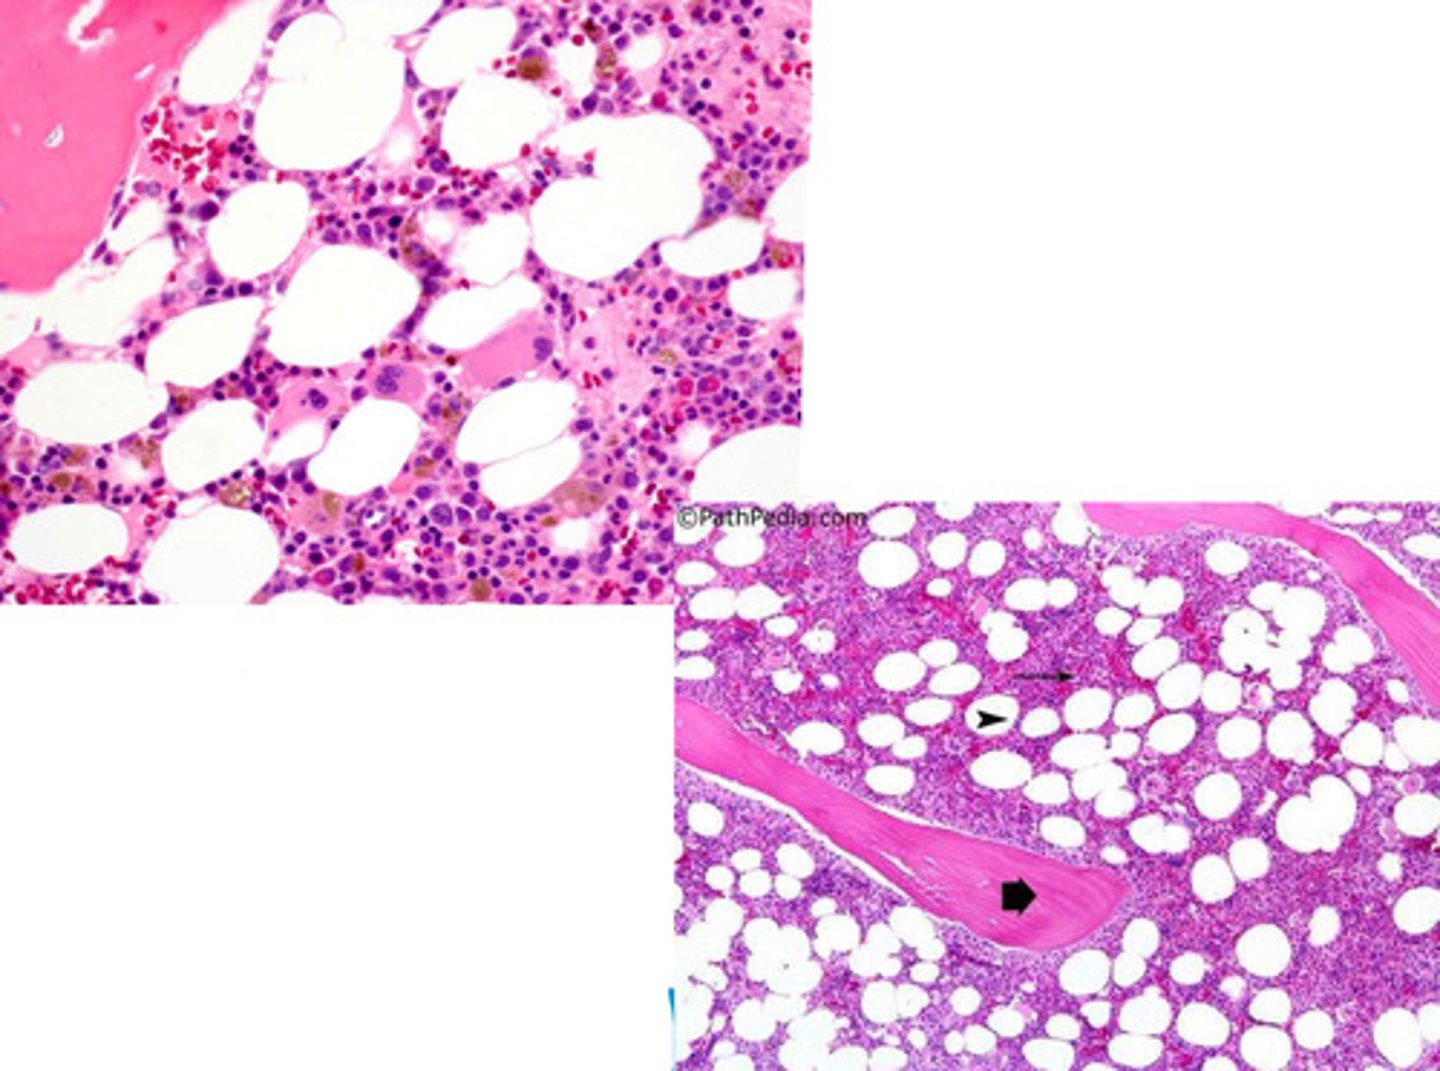

yellow bone marrow

what is this?

adipose tissue

what are the components of the yellow bone marrow?